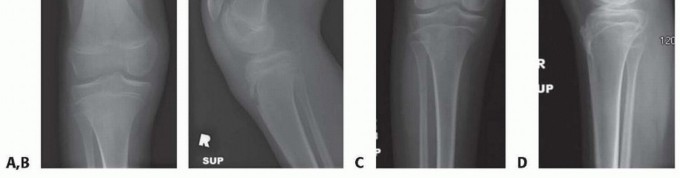

- ###

- FIG 2 • A. A 13-year-old girl with knee pain and difficulty with ambulation secondary to genu valgum. B. Standing AP radiograph of her lower extremities demonstrating bilateral genu valgum with abnormal LDFA bilaterally and an abnormal MPTA on the right tibia. She was indicated for bilateral medial distal femoral

- guided growth and right medial proximal tibia guided growth. C. Standing AP radiograph at 7 month postoperatively demonstrates normalization of her mechanical axis. (Courtesy of UW Pediatric Orthopaedics.)

- FIG 3 • A. A 7-year-old boy with traumatic amputation from a lawn mower injury with varus deformity causing difficulty with prosthetic wear. B,C. Although the CORA was a result of fracture malunion proximal to the distal femoral physis, guided growth was chosen as an alternative to osteotomy to straighten the limb and to improve prosthetic wear.

- FIG 4 • A,B. A 13-year-old boy with spastic diplegia who ambulates with a crouch knee gait, hamstring contracture, and knee flexion contracture. C,D. The patient was able to achieve full extension after hamstring release and anterior distal femoral guided growth with two modular implants placed next to the patella. To place these implants, two peripatellar incisions are needed to allow intra-articular placement of the devices across the physis and to ensure that no patellar contact ensues. (Courtesy of UW Pediatric Orthopaedics.)

- FIG 5 • A. An 8-year-old boy with 20 degrees residual equinus and talus dysmorphology after revision posterior medial release. B,C. Anterior distal tibia guided growth was performed after a CT scan ensured appropriate sizing of the epiphysis. In this procedure, a modular implant is placed by putting a guide pin into the distal tibia epiphysis and then a cannulated screw is placed. D,E. Two years postoperatively, the patient now has 10 degrees of ankle dorsiflexion. (Courtesy of UW Pediatric Orthopaedics.)